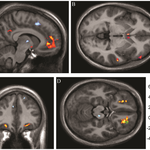

What's more universal in culture than a "thumbs up"? To our brains, whether we seem to have a cultural familiarity or not, it isn't familiar at all, says new research in Human Brain Mapping. People seem to react quickly and intuitively to body language, tone of voice and gaze but gestures are different, at least when the gesturer offers no other cues.    Less surprisingly, the new study also found that same-race interaction leads to greater activity in the mirror neuron system, a region of the brain linked to subconscious imitation. Neuroscientists at USC and Peking University…